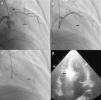

O procedimento descrito tem com certeza pequenas diferenças em relação ao usado por outros centros e operadores, embora os passos fundamentais sejam comuns a todos que privilegiem uma técnica segura. Queremos destacar três alterações que contribuíram para um aumento da sua segurança e para a melhoria dos resultados atuais face aos descritos nas primeiras séries de doentes. A primeira consiste na utilização de menor quantidade de álcool, diminuindo a área de necrose e com isso a possibilidade de afetar o tecido de condução auriculoventricular. Também a ideia de ter um objetivo imediato de redução do gradiente, repetindo as injeções de álcool se necessário, foi abandonada a favor da avaliação dos resultados após a cicatrização e remodeling do septo. A segunda foi introduzida por Faber em 1998, quando utilizou a injeção de contraste intramiocárdio e a ecocardiografia transtorácica para identificar corretamente a artéria septal alvo e excluir a afetação de regiões remotas do miocárdio14. Este é atualmente um passo de grande relevância no procedimento, como exemplifica a nossa experiência em que a artéria alvo foi modificada em 10% dos doentes (Figura 2), sendo que em três doentes (não incluídos nesta população) a intervenção foi abandonada por não existir uma septal alvo em função da informação ecocardiográfica. Por fim, a introdução de scores de risco para o estabelecimento do bloqueio da condução auriculoventricular de alto grau veio permitir distinguir os doentes em que é correto aguardar pela resolução da fase de edema do septo, após a qual se assiste na maioria dos casos à resolução da perturbação da condução, daqueles em que se deve optar logo pela colocação de pacemaker definitivo13.

Alteração da septal alvo após injeção de contraste intracoronário. a) Cateterização seletiva da segunda septal. b) Cateterização selectiva da primeira septal. c) Opacificação da parte direita do septo após injeção de contrate na segunda septal. d) Opacificação da região adequada do septo, porção basal em relação com o folheto anterior da válvula mitral, com injeção de contraste na primeira septal.